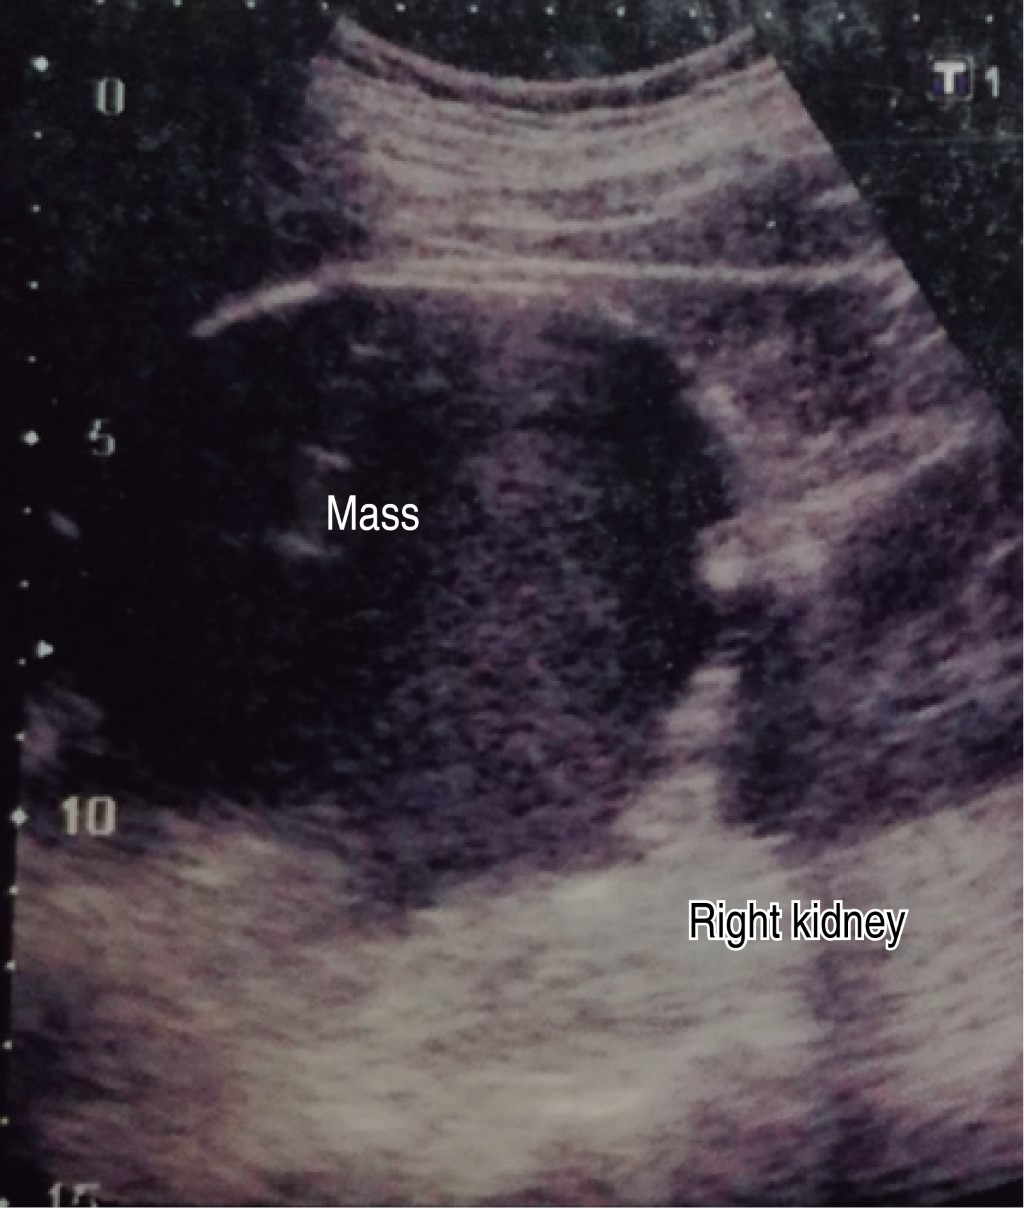

An ultrasound scan done in March reports liver of normal size, shape, and situation with an irregular lower right border, of heterogeneous echogenicity due to the presence of a rounded shape anechoic mass with well-delimited borders and thin walls suggestive of a simple cyst (Figures 1 and 2).

Figure 1

Figure 2